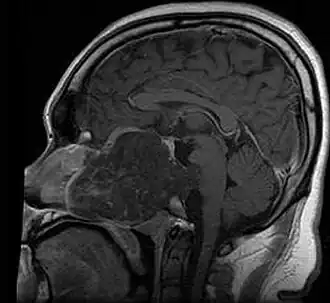

Chordoma is a rare slow-growing neoplasm (cancer) that arises from cellular remnants of the notochord in the bones of the skull base and spine. The evidence for the notochordal origin of chordoma is the location of the tumors (along the neuraxis), the similar immunohistochemical staining patterns, expression of brachyury, and the demonstration that notochordal cells are preferentially left behind in the clivus and sacrococcygeal regions when the remainder of the notochord regresses during fetal life.

In layman's terms, chordoma is a type of bone cancer, and is classified as a sarcoma.[1] Chordomas are sometimes mistakenly referred to as a brain, brainstem or spinal cord tumors due to their location near those critical structures, but they are not derived from nervous tissue.

Chordomas can arise from bone in the skull base and anywhere along the spine. The two most common locations are cranially at the clivus and in the sacrum at the bottom of the spine.[2] Very rarely, chordomas present outside of the skull base or spine; these are called extra axial chordomas.[3]